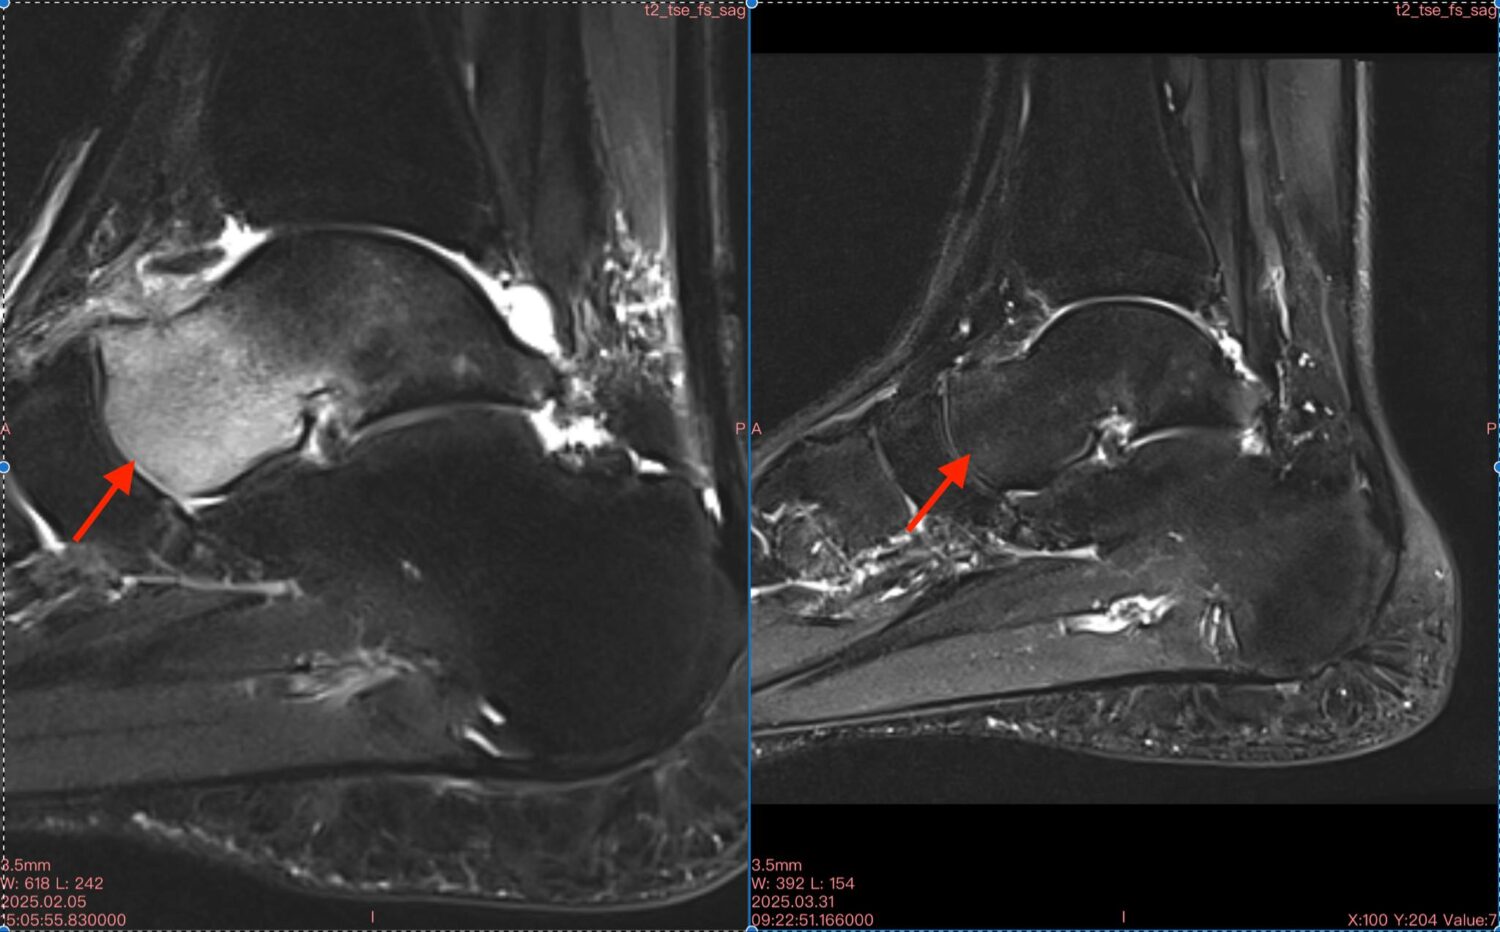

Μαγνητικές ασθενών με οστικό οίδημα πριν (αριστερή φωτογραφία) και μετά (δεξιά φωτογραφία) την θεραπεία με διαμαγνητική αντλία: